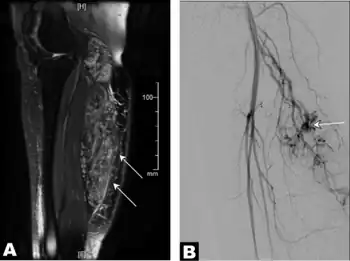

| a) Image with intravenous gadolinium contrast demonstrated an infiltrative vascular malformation in right gastrocnemius b) digital subtraction angiogram of right leg in a lateral projection during the arterial phase revealed arteriovenous shunting | |